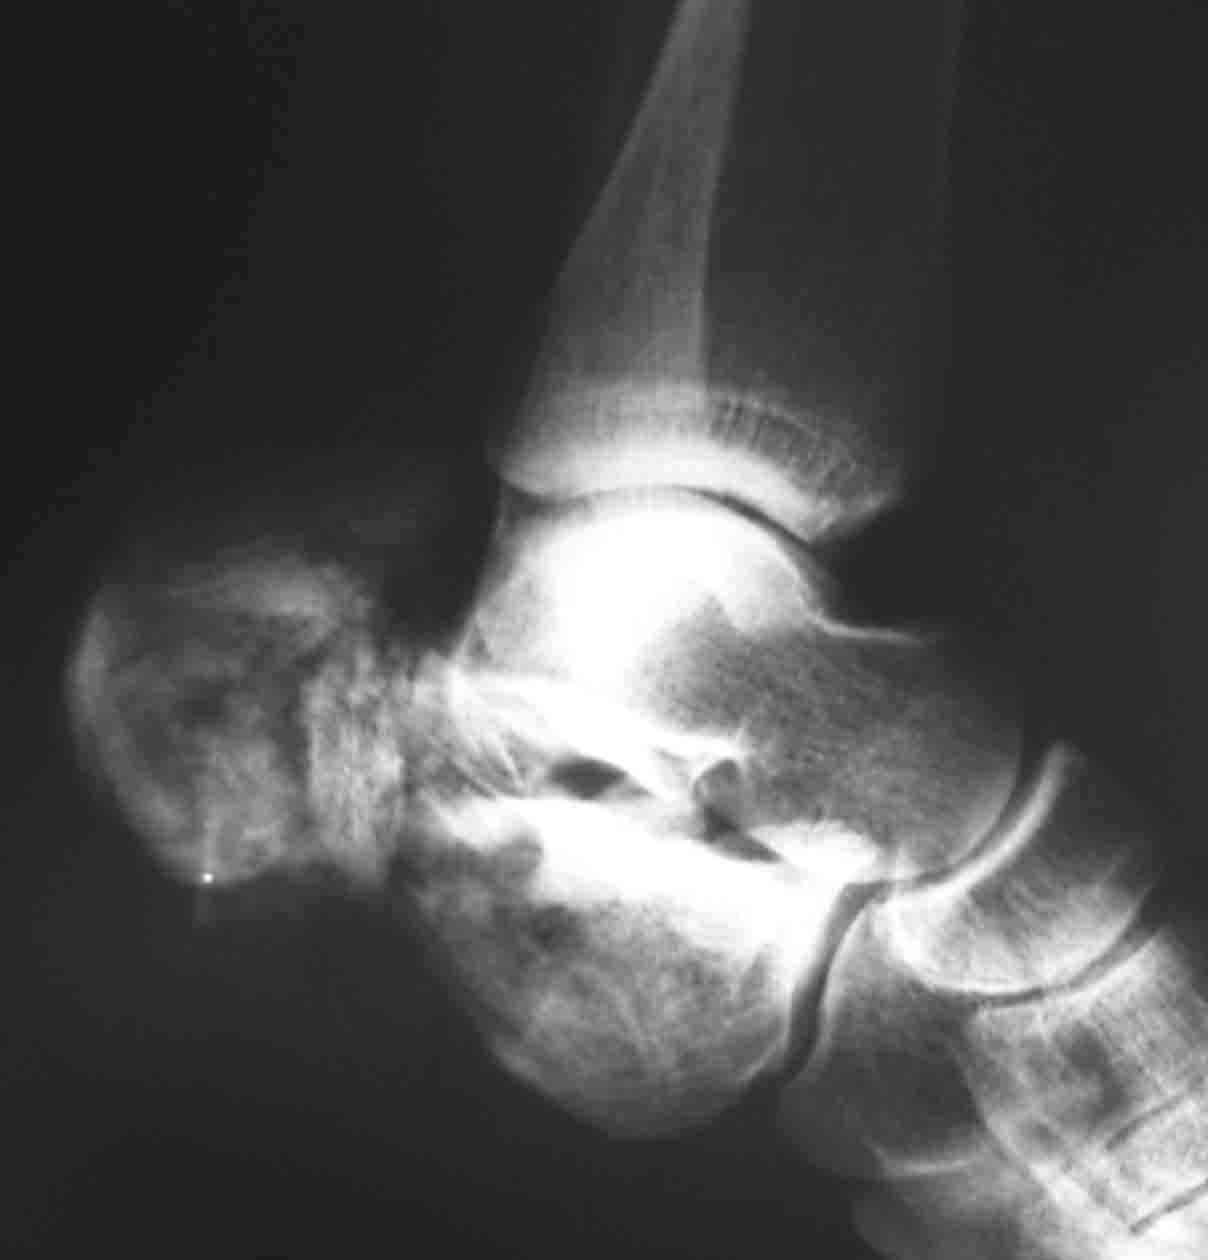

Пациентка 26 лет поступила в больницу 9 дней назад после кататравмы (падение с 4-го этажа) Тяжелая сочетанная травма: Ушиб головного мозга средней тяжести.З/полифокальный перелом таза (оскольчатый чрезвертлужный справа, латеральной массы крестца слева со смещением отломков. З/оскольчатый перелом н/3 правого бедра. З/оскольчатый перелом правой пяточной кости. Тупая травма живота - разрыв слизистой толст кишечника, кисты яичника.

При поступлении - лапаротомия, ушивание ран кишечника, резекция кисты; скелетное вытяжение за правую н/конечность (бугрист б/б кости) На 2-й день на таз наложен стержневой аппарат из "того что было" (по паре стержней в подвздош кости) - естественно, при таком переломе фиксации таким аппартом практически никакой. Пациентка 2 дня назад переведена из реанимации в травм отделение, состояние средней тяжести, показатели красной крови - эритр 2,7; Гб - 75 г/л; Спицевое вытяжение за б/вертел не накладывали из-за возможности инфицирования бедра (пациенка по комплекции довольно упитанная) Встает вопрос - что и в какой последовательности делать с поврежденными сегментами скелета? Думали о варианте: Первым этапом - погружной остеосинтез бедра (DCS? интерлокинг?)и ,возможно, пяточной кости.Вторым этапом - стержневой остеосинтез таза с бедренным модулем (внутренний остеосинтез таза, думаю, по соматике пациентки будет возможен не скоро)